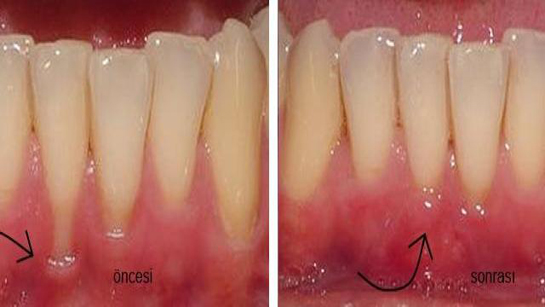

İyileşme Süreci Diş çekimi sonrası iyileşme süreci, bireyden bireye değişiklik göstermekle birlikte genellikle aşağıdaki aşamalardan oluşur:

Senin de belirttiğin gibi, tükürmemek ve ağız çalkalamamak, kanamanın durmasına yardımcı olmak adına son derece önemli. Bu bilgiyi zamanla kavramak, iyileşme sürecinde kaygıların azalmasına neden oluyor. Soğuk uygulamanın da etkilerini gözlemlemen, şişlik ve ağrıyı azaltma konusunda ne kadar faydalı olabileceğini gösteriyor.